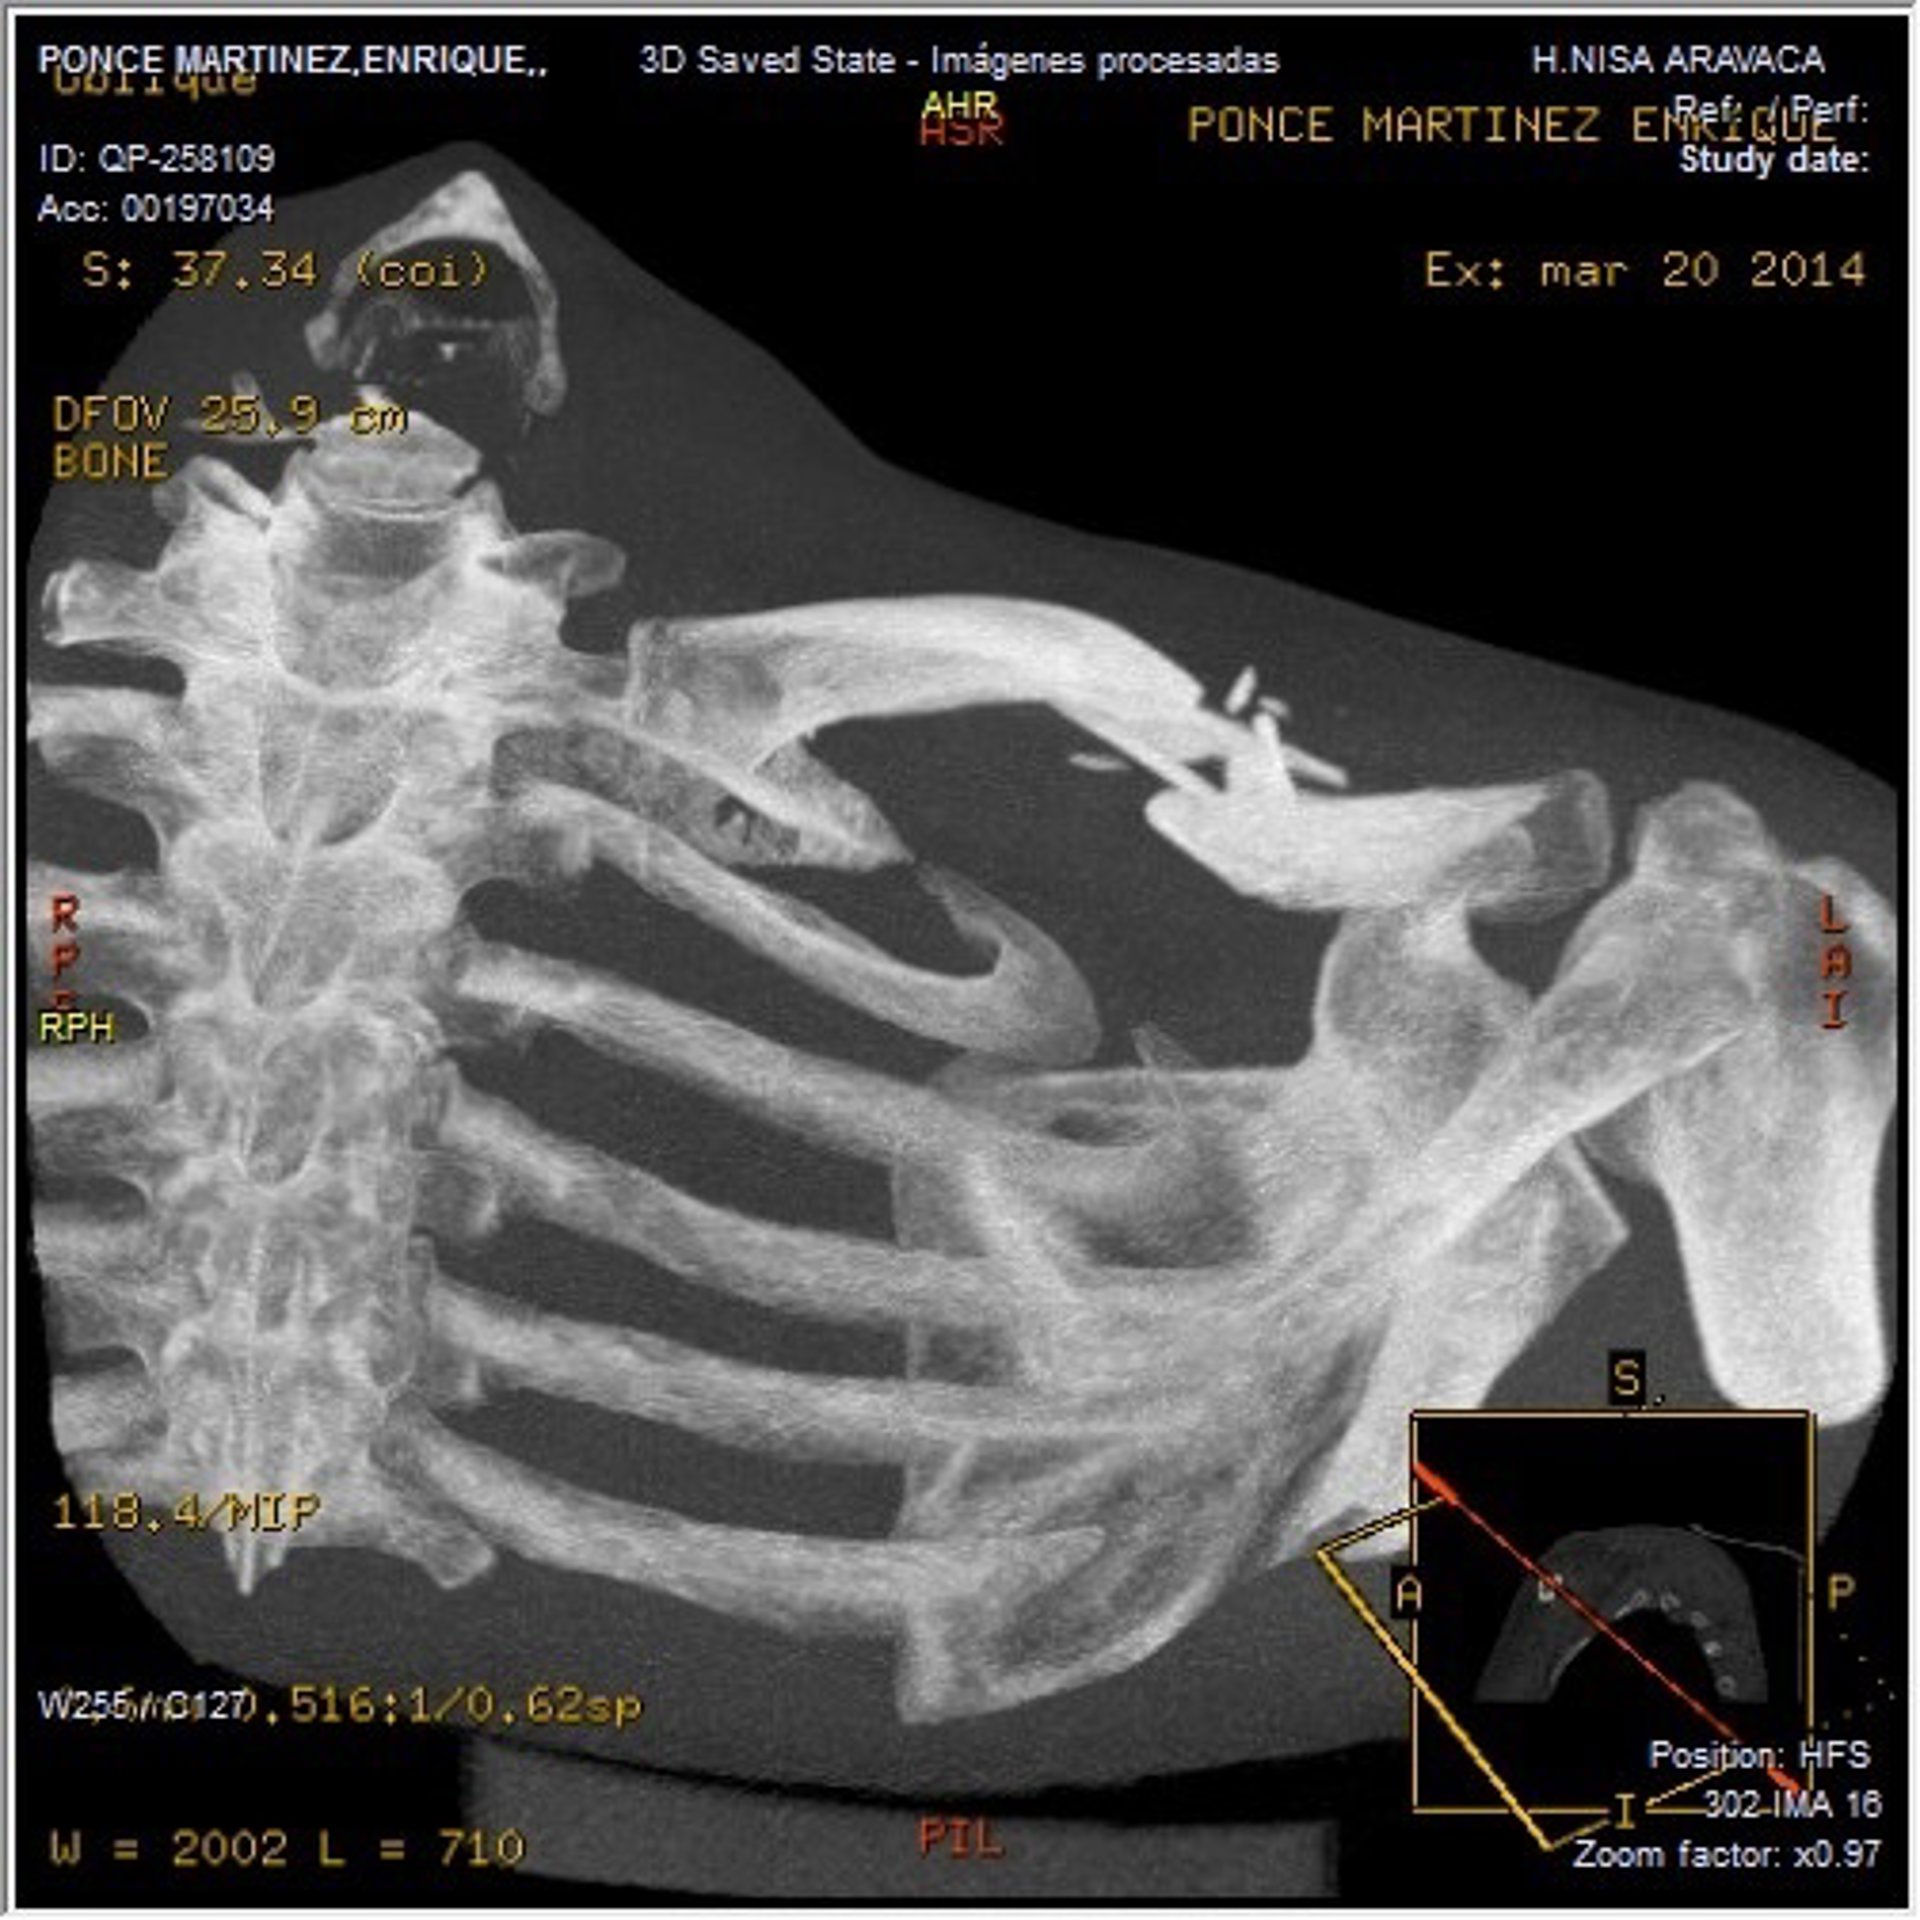

Clavícula Enrique Ponce

El diestro Enrique Ponce evoluciona "muy favorablemente" después de pasar "una buena noche" tras la operación de fractura de clavícula a la que ha sido sometido en el Hospital Nisa Pardo de Aravaca (Madrid), según el parte médico emitido por el centro hospitalario.

Ponce ha sido visitado a primera hora por el doctor Villamor, quien ha constatado "el excelente estado", tanto de la lesión de clavícula izquierda como la provocada por la cornada en la axila derecha, supervisada también por el doctor José Ramón March, cirujano viscular del mismo hospital.